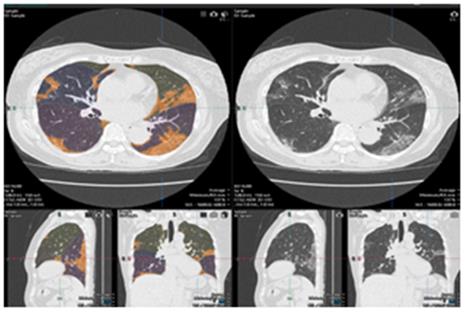

日本藤田醫(yī)科大學(xué)攜手佳能醫(yī)療共同開發(fā)新冠快速檢測(CT)系統(tǒng)

日本藤田醫(yī)科大學(xué)放射線學(xué)教授大野良司與佳能醫(yī)療系統(tǒng)株式會社合作開發(fā)了基于CT肺部圖像的新冠肺炎解析軟件。... -